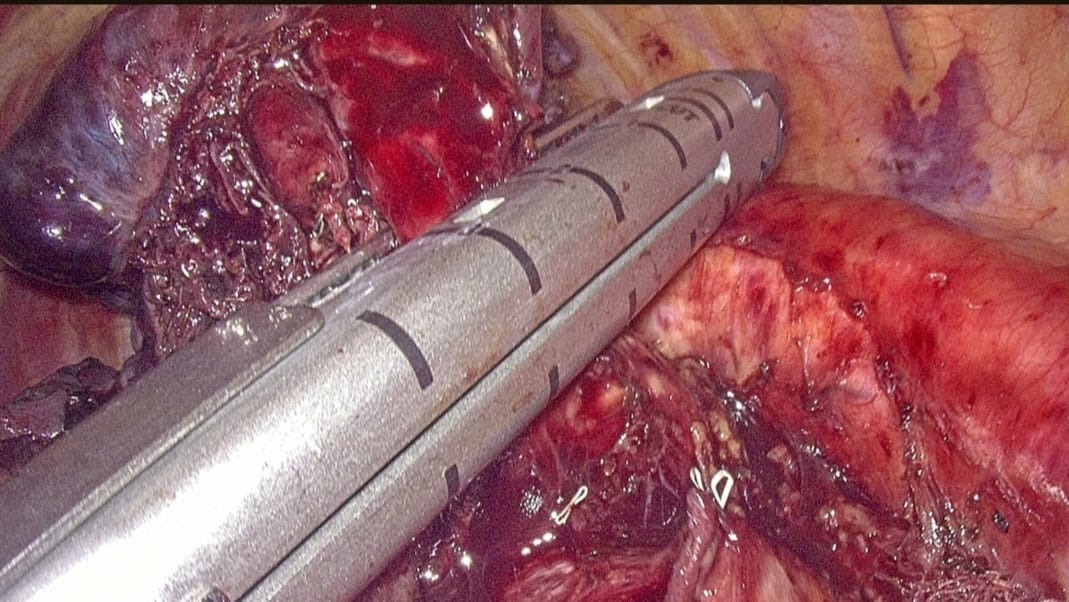

Surgical Staplers

- Advanced staplers allow safe resections of organs like bowel, stomach, and lung tissue

- Helps in anastomosis of different organs after resections

- Less blood loss

- Reduced surgery time

- Lower complication risk